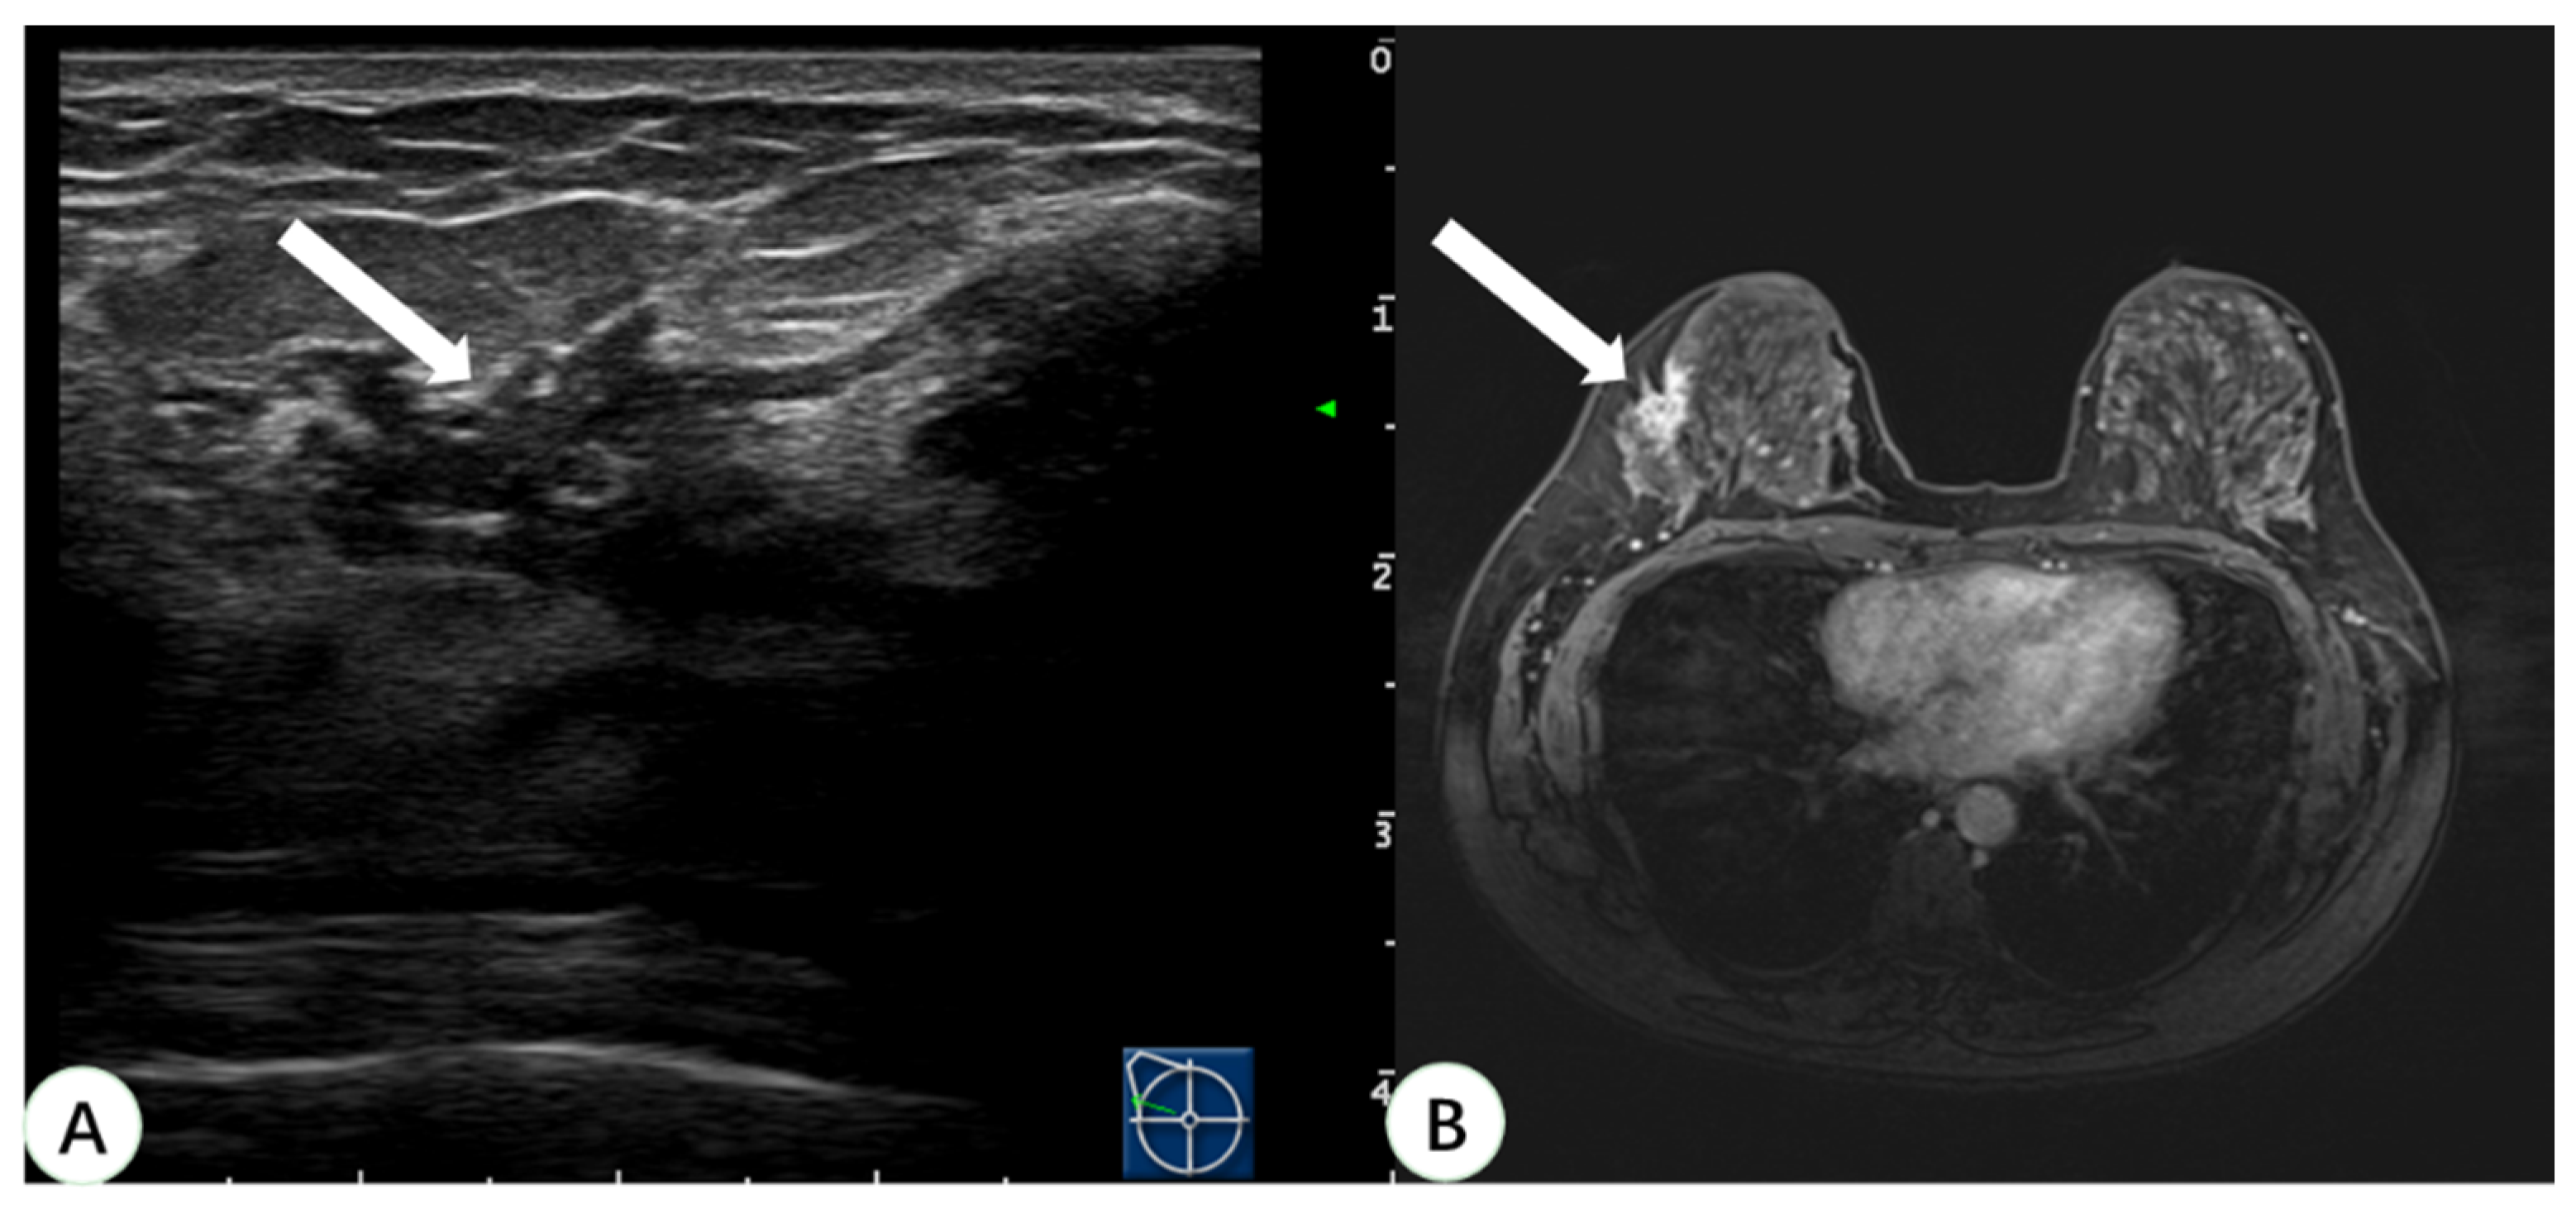

Figure 4.

A 46-year-old woman with dense breast tissue underwent virtual navigation: (A) Real-time US with virtual navigation detected the corresponding lesion (arrow) in the left breast at the 12-o’clock position 2 cm from the nipple, which underwent ultrasound-guided biopsy; (B) CE-MRI showed a suspicious enhanced irregular lesion (arrow) in the upper left breast, undetected at second-look US. Pathology obtained by US-guided biopsy with virtual navigation demonstrated a ductal carcinoma in situ. US = ultrasound; CE-MRI = contrast-enhanced magnetic resonance imaging.